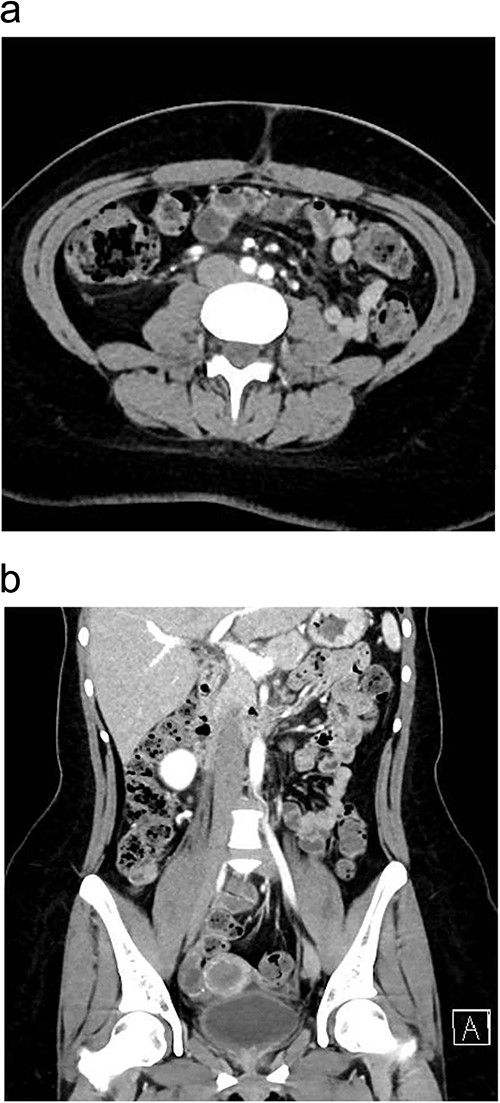

The patient was managed with a low-fat diet, octreotide, and close monitoring of drain output. Over the following days, the drain output gradually diminished and became serous in color. By the third postoperative day, the drain was removed, and patient was discharged from the hospital in good condition. During follow-up in the outpatient clinic, the patient reported no active complaints and was in good health. A follow-up enhanced CT scan of the abdomen and pelvis, performed 1 month after discharge, showed no signs of recurrence (Fig. 3a and b). Histopathology results of the removed appendix confirmed the diagnosis of acute appendicitis.

One month postoperatively enhanced CT abdomen and pelvis with axial (a) and coronal (b) views showing resolution of inflammation and no signs of recurrence of chyloperitoneum.